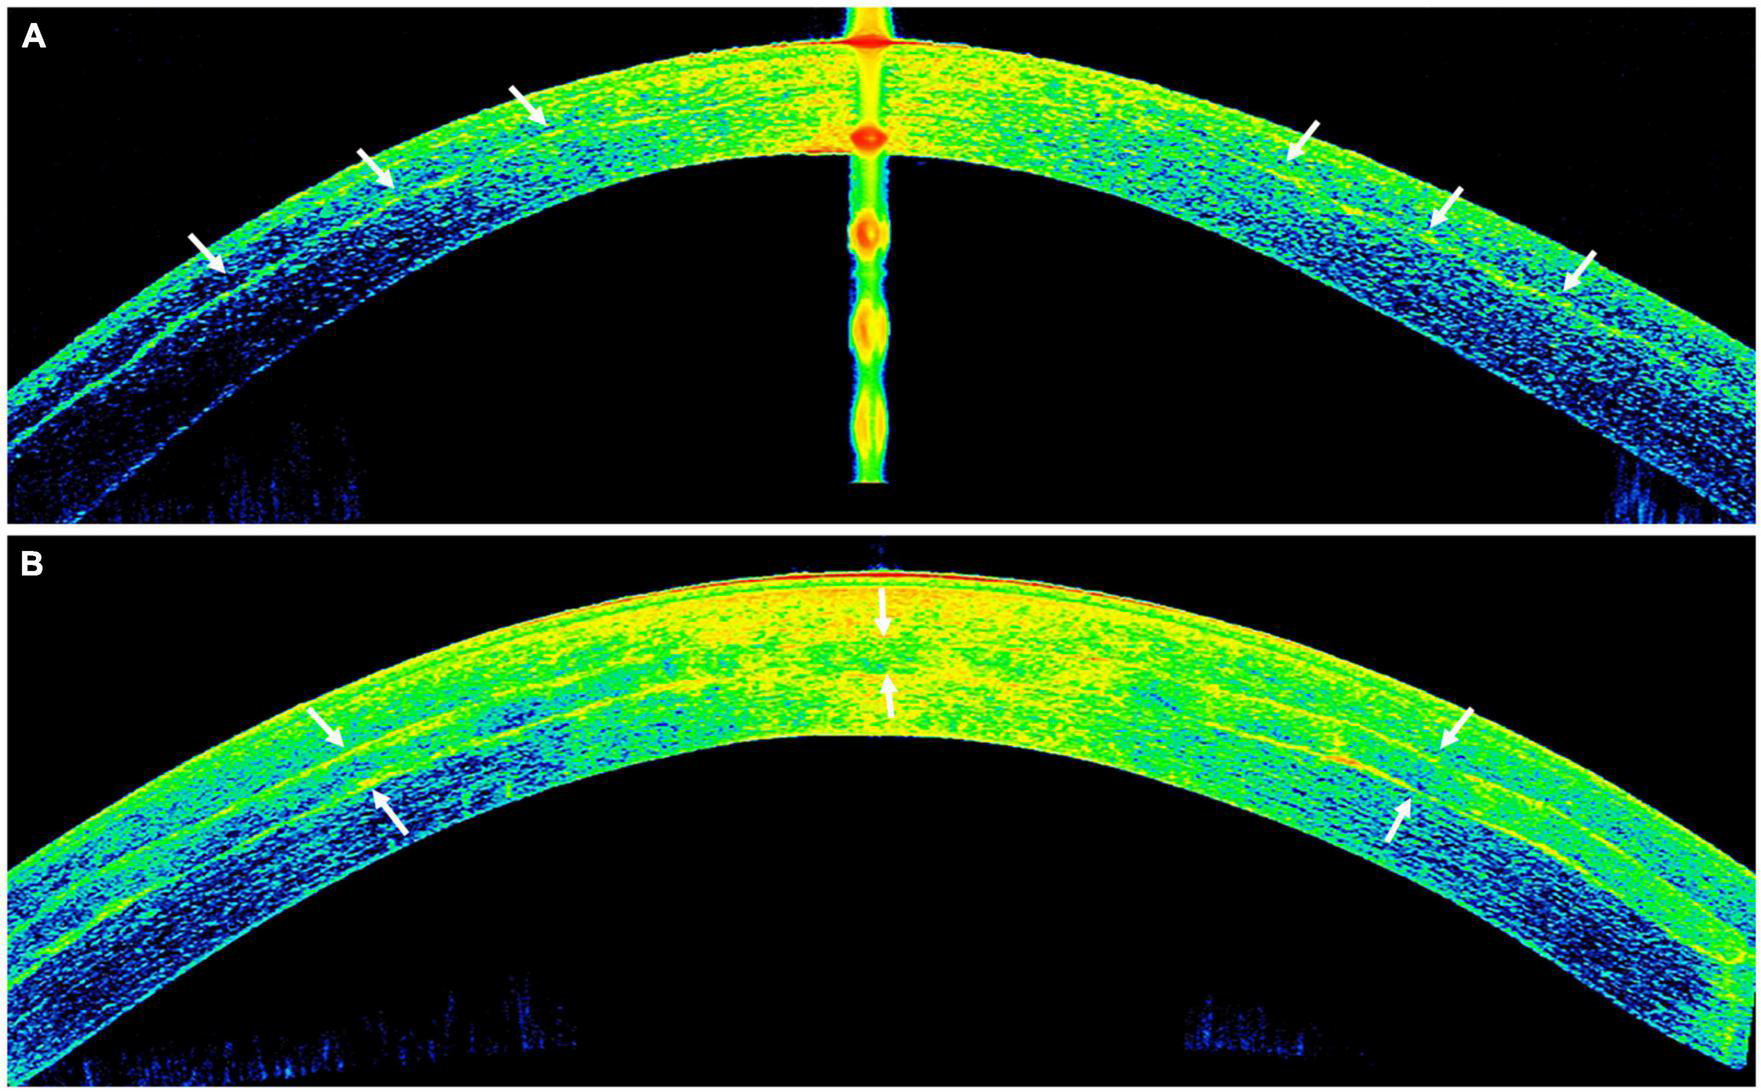

FIGURE 7

Anterior segment optical coherence tomography (AS-OCT) images demonstrating the outcome of implanted autologous adipose derived adult stem cells (ADASCs) in advanced keratoconus. (A) An ASOCT image showing the effect of the cellular therapy of the corneal stroma by an intrastromal implantation of autologous ADASCs in a patient with advanced keratoconus at 6 months post-treatment. Observe the hyperreflective band of neo-collagen (around 15 μm thickness) at the level of the stromal pocket (arrows). (B) An ASOCT image showing the corneal stromal enhancement by an intrastromal implantation of a decellularized lamina of human corneal stroma (arrows) colonized with autologous ADASC in a patient with advanced keratoconus at 12 months post-treatment.